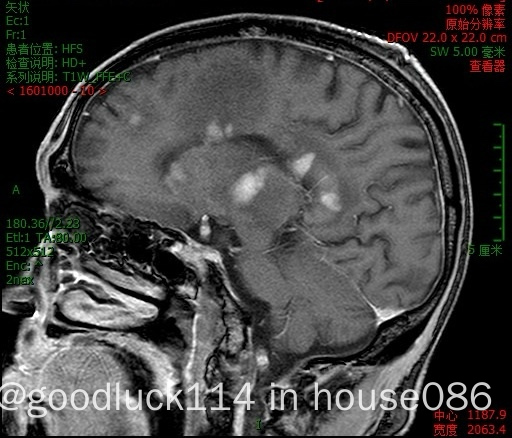

高龄取不了病理,医院做不了pet-ct,做了头颅ct和mri,发现颅内占位性病变,怀疑原发或转移,但胸部ct腹部ct和肿瘤标志物都没有明显异常,也没有除神经系统外其他系统的症状,mri增强结果不像是胶质瘤,高度怀疑是原发性中枢淋巴瘤。